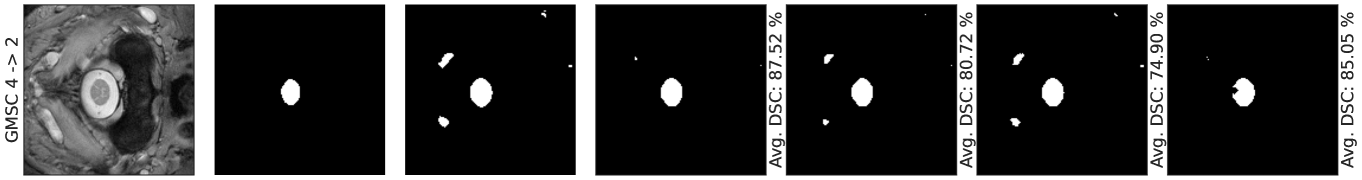

Figure 3 shows these improvements, demonstrating how our method effectively refines and completes erroneous initial predictions from the pretrained model. This is enabled by the progressive updates guided by estimated energy values, and Fig. 4 illustrates the iterative refinements.

Figure 4 illustrates the progression of improvements by showing the estimated energy predictions across iterations. Our region-based energy model accurately identifies regions with undesired shapes by assigning them high energy values in row 2, guiding the model adaptation through iterative computation of Eq. 8 to align with the uniform low energy reference. The progressive nature of our update serves as a strength, as gradient updates are local approximations of the loss landscape. Performing a large update may overshoot, which motivates our choice to progressively adapt the model parameters. This is validated by Tabs. 1, 2, 3 and 4 and qualitative results Fig. 3. Our energy model at test time also provides a coarse level of interpretability in the update as the adaptation is localized to each patch, e.g., when a patch exhibits low energy, the parameters are not updated and errors can be identified visually as energy maps. This further demonstrates the superiority of our method, which directly utilizes an energy-based model to enforce a shape prior by distinguishing in-distribution from out-of-distribution shapes robustly across iterations. This contrasts with existing methods like TEA, which use energy-based models to generate rather than discriminate fake shapes. Consequently, our method is more computationally efficient (see Supp. Mat.) as it does not require generative steps.